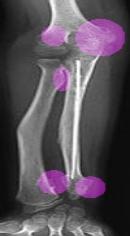

Ankles x-rays

X-rays of fixators placed in Legs and Arm

The MHE Research Foundation's X-Ray & Image Gallery

These X-rays & Images were obtained from a variety of children with MHE / MO / HME